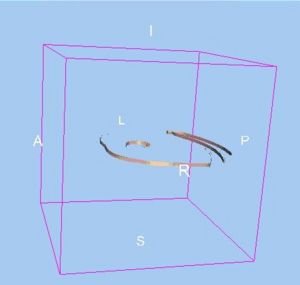

Seeing More by Showing Less: Orientation-Dependent Transparency Rendering for Fiber Tractography Visualization

Publication: PLoS One. 2015 Oct 7;10(10):e0139434. PMID: 26444010 | PDF Authors: Tax CM, Chamberland M, van Stralen M, Viergever MA, Whittingstall K, Fortin D, Descoteaux M, Leemans A. Institution: Image Sciences Institute, University Medical Center Utrecht, Utrecht, The Netherlands. Background/Purpose: Fiber tractography plays an important role in exploring the architectural organization of fiber trajectories, both in fundamental neuroscience and in clinical applications. With the advent of diffusion MRI (dMRI) approaches that can also model "crossing fibers", the complexity of the fiber network as reconstructed with tractography has increased tremendously. Many pathways interdigitate and overlap, which hampers an unequivocal 3D visualization of the network and impedes an efficient study of its organization. We propose a novel fiber tractography visualization approach that interactively and selectively adapts the transparency rendering of fiber trajectories as a function of their orientation to enhance the visibility of the spatial context. More specifically, pathways that are oriented (locally or globally) along a user-specified opacity axis can be made more transparent or opaque. This substantially improves the 3D visualization of the fiber network and the exploration of tissue configurations that would otherwise be largely covered by other pathways. We present examples of fiber bundle extraction and neurosurgical planning cases where the added benefit of our new visualization scheme is demonstrated over conventional fiber visualization approaches. Funding:

|